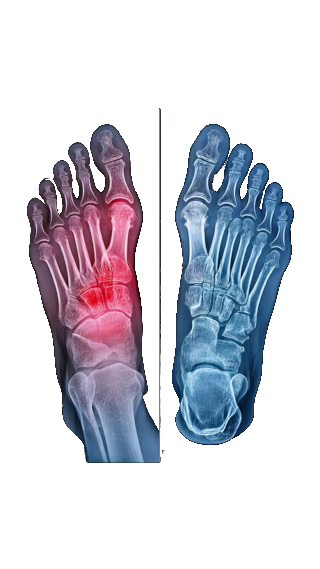

Podologia ortopedyczna zajmuje się diagnozowaniem wad narządu ruchu, wspomaganiem rozwoju układu mięśniowo-szkieletowego u dzieci i utrwalania prawidłowej postawy. Wspiera sportowców w poprawianiu osiągnięć oraz w profilaktyce i leczeniu kontuzji poprzez ustawienie stóp i całego ciała za pomocą indywidualnych wkładek ortopedycznych.

Wielu z nas bagatelizuje problem związany z wadami i zniekształceniami stóp. Nie zdajemy sobie jednak sprawy z tego, jak istotne dla naszego zdrowia jest prawidłowe skorygowanie niefizjologicznie zbudowanej lub ustawionej stopy. Niewłaściwie rozłożony na stopy nacisk przenosi bowiem powstające przeciążenia na wyższe poziomy łańcucha kinematycznego: stawy skokowe, kolana, biodra, miednicę, kręgosłup, głowę.

Udowodniony jest wpływ ustawienia stóp na stawy skroniowo-żuchwowe (może np. wywoływać ból zdrowych zębów, zgrzytanie, powodować wady zgryzu, bóle głowy). Nawet jeśli deformacje są (jeszcze) niebolesne warto zdecydować się na wizytę u podologa, który oceni sytuację i zaprojektuje odpowiednie wkładki ortopedyczne.